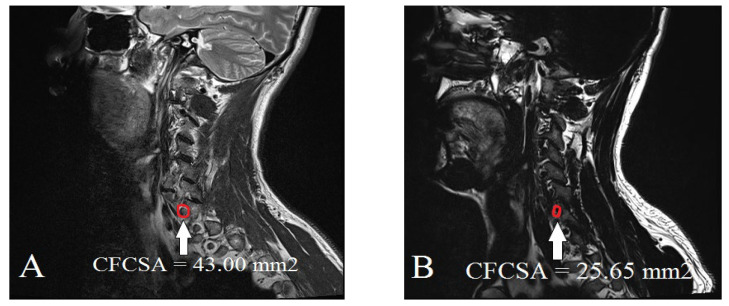

Background: Cervical foraminal bony stenosis (CFBS) is a common degenerative spinal condition that causes radicular pain and functional impairment in the upper extremities. Accurate and objective diagnosis of CFBS remains challenging due to the absence of standardized morphometric criteria. This study aimed to determine an optimal cut-off value for the cervical foraminal cross-sectional area (CFCSA) at the C5/6 level as a diagnostic indicator of CFBS. Methods: We conducted a retrospective case-control study including 154 patients aged 50 years or older with clinically and radiologically confirmed CFBS and 150 age-matched asymptomatic controls. Cervical spine magnetic resonance imaging (MRI) was performed in all subjects and CFCSA measurements were obtained from sagittal T2-weighted images using a standardized protocol. Group differences were analyzed using t-tests and diagnostic performance was assessed using receiver operating characteristic (ROC) curve analysis. Results: The mean CFCSA was significantly lower in the CFBS group (25.65 ± 7.19 mm2) compared to the control group (43.00 ± 8.38 mm2; p < 0.001). ROC analysis identified a CFCSA threshold of 33.02 mm2 as the optimal cut-off point for predicting CFBS, yielding a sensitivity of 86.4%, a specificity of 86.7%, and an area under the curve (AUC) of 0.94 (95% CI: 0.91-0.96). Conclusions: These findings suggest that CFCSA is a robust and reproducible morphological parameter for evaluating foraminal stenosis. The proposed cut-off may enhance diagnostic accuracy and aid in clinical decision-making for patients presenting with C6 radiculopathy. However, given this study's retrospective, single-center design, further validation through multicenter, prospective studies across multiple cervical levels is warranted.